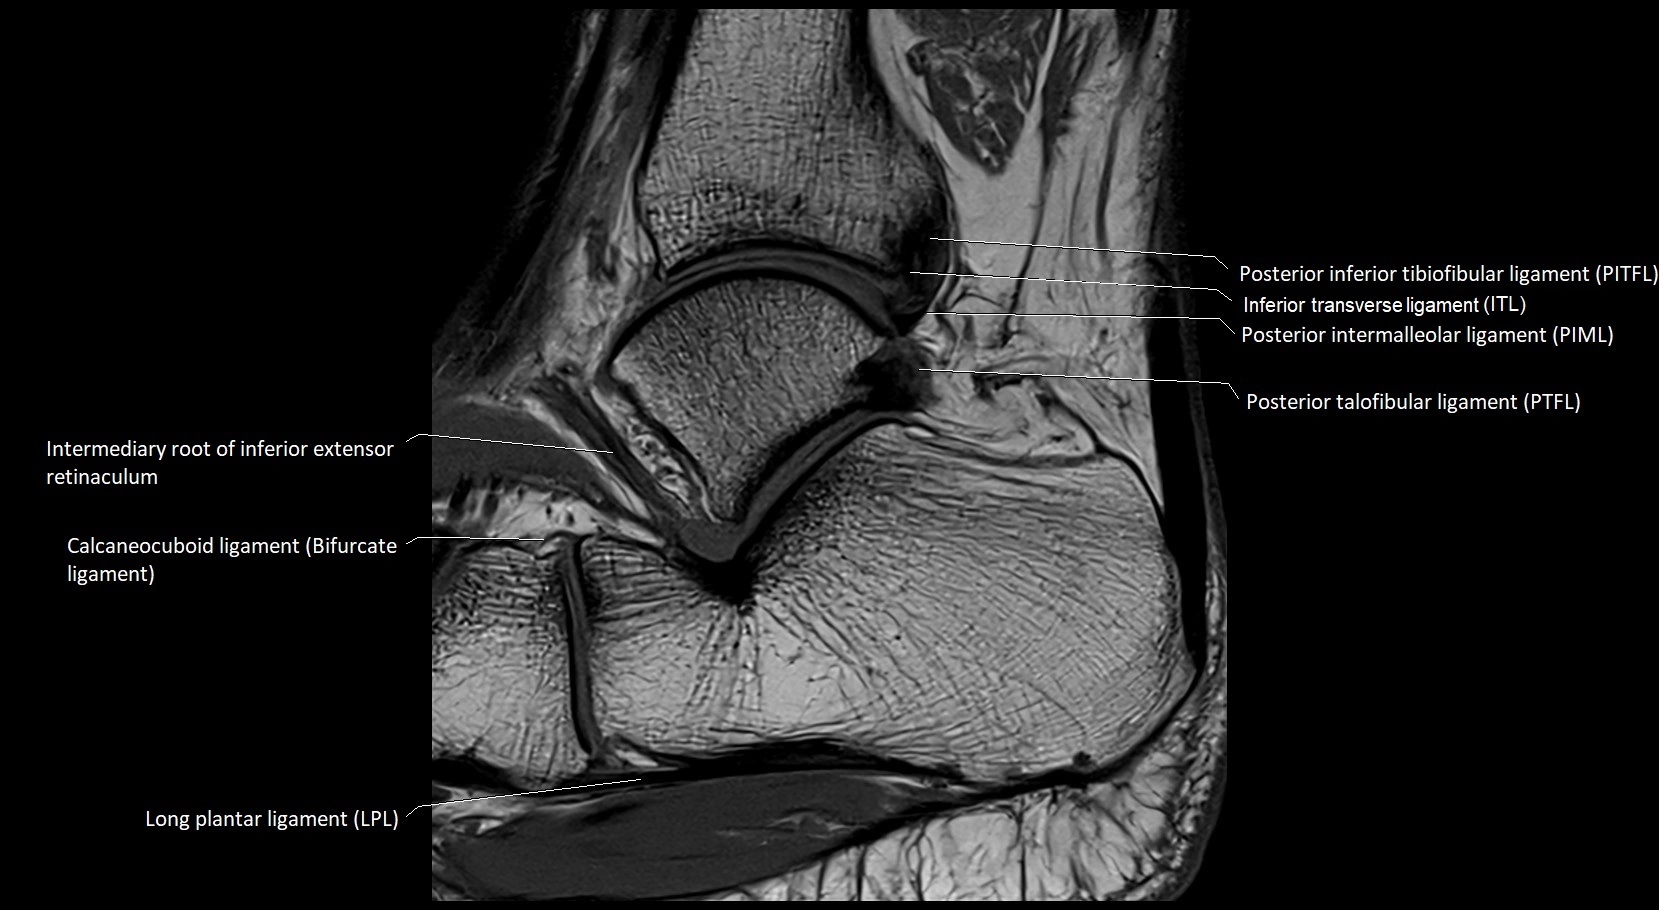

MRI image

image